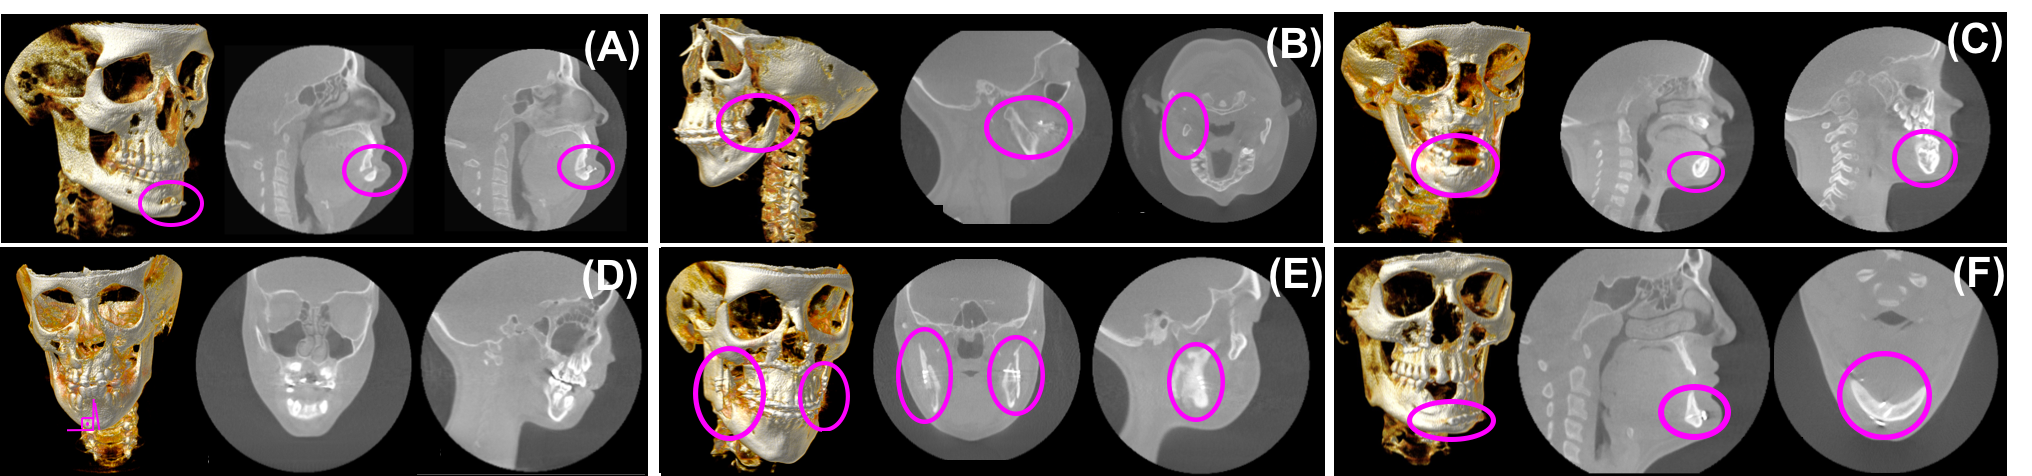

(adult).

The main reason for this research gap is high anatomical variability in the shape of these bones due to their deformities in such patient populations. Figure 2 shows some of the known CMF deformities and artifacts, including missing bones (hence missing landmarks) or irregularities from the underlying disease or the surgical treatment (Figures 2a-2b), varying number of teeth including missing teeth and unerupted deciduous teeth distorting the anatomy (Figures 2c-2d), and surgical interventions such as implants or surgical plates and screws that are necessary to treat the injury or deformity (Figures 2e-2f). Other reasons are image/scanner based artifacts/problems such as noise, inhomogeneity, truncation, beam hardening, and low resolution. Unlike existing methods focusing on dental applications with relatively small anatomical variations, there is a strong need for creating a general purpose, automated CMF image analysis platform that can help clinicians create a segmentation model and find anatomical landmarks for extremely challenging CMF deformities. Due to the lack of a general purpose image analysis platform, clinicians still perform their analysis either manually or semi-automatically with limited software support. This process is extremely tedious and prone to reproducibility errors.